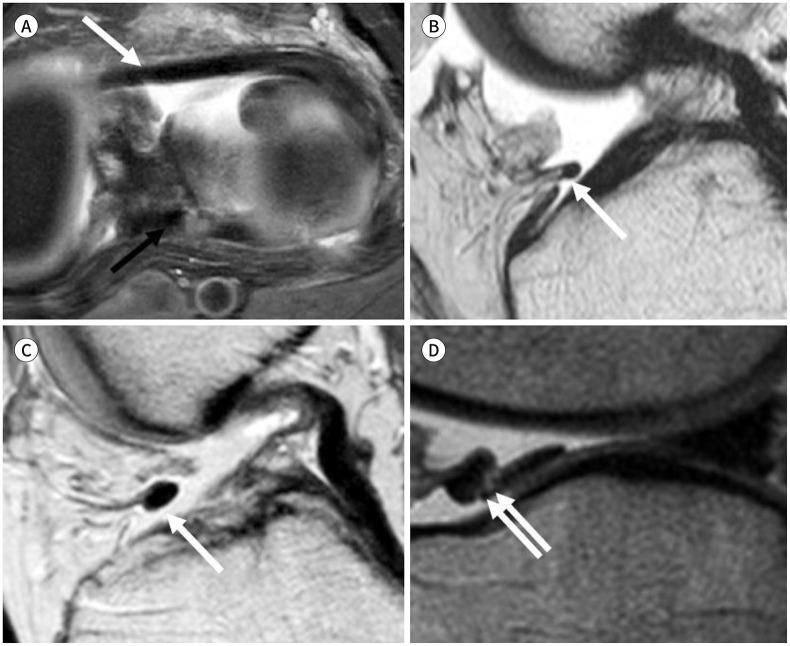

To accurately interpret knee MRI, it is important not only to know the basic meniscal anatomy but also to distinguish it from that under pathological conditions. Thus, it would be helpful to know the normal meniscus variants (false positives) that could be mistaken for meniscal tears, and tears that could easily be missed and incorrectly diagnosed as normal (false negatives). False positives include synovial recesses, meniscal flounce, the relationship between the popliteus tendon and lateral meniscus, transverse ligament, the anterior root of the meniscus, and meniscofemoral ligament. False negatives include focal radial tears, flap tears, posterior root tears, meniscocapsular separation, and discoid meniscal tears. In this pictorial essay, we reviewed the imaging data obtained in the aforementioned cases.

为了准确解读膝关节磁共振成像(MRI),不仅要了解半月板的基本解剖结构,还要将其与病理状态下的情况区分开来。因此,了解可能被误诊为半月板撕裂的正常半月板变异(假阳性)以及容易被漏诊并错误诊断为正常情况(假阴性)的撕裂情况会有所帮助。假阳性包括滑膜隐窝、半月板皱襞、腘肌腱与外侧半月板的关系、横韧带、半月板前根和半月板股骨韧带。假阴性包括局灶性放射状撕裂、瓣状撕裂、后根撕裂、半月板关节囊分离和盘状半月板撕裂。在这篇图文文章中,我们回顾了上述病例中获得的影像数据。